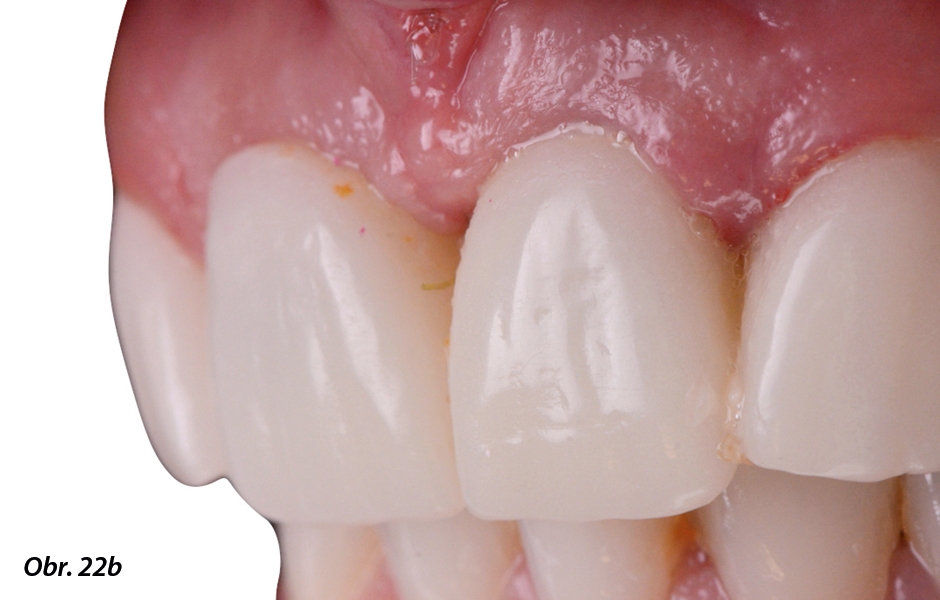

V laboratoři byly připraveny provizorní individuální abutmenty a pryskyřičné provizorní náhrady (obr. 19, 20). Velmi pečlivě se dbalo na přípravu subgingiválního emergence profilu, který měl na gingivální úrovni poskytnout hladký přechod z platformy implantátu na přirozený tvar zubu a podepřít a vytvarovat gingivu kolem implantátu (obr. 21–23).

Po uplynutí 6 měsíců byly měkké tkáně zhojeny a přizpůsobeny provizorním korunkám (obr. 24–26).